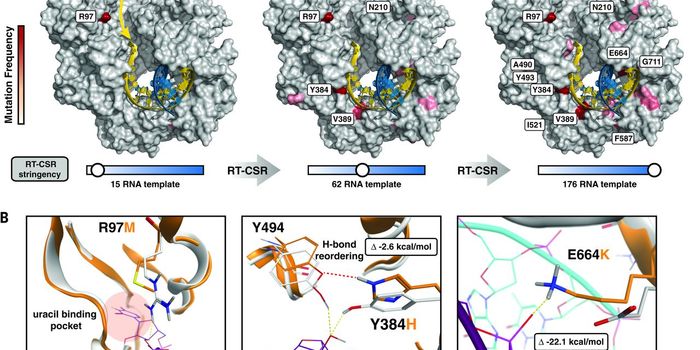

SEP 14, 2017CancerLarry King, the famed talk show host, recently revealed his diagnosis of Stage 1 lung cancer. King then underwent surger ...